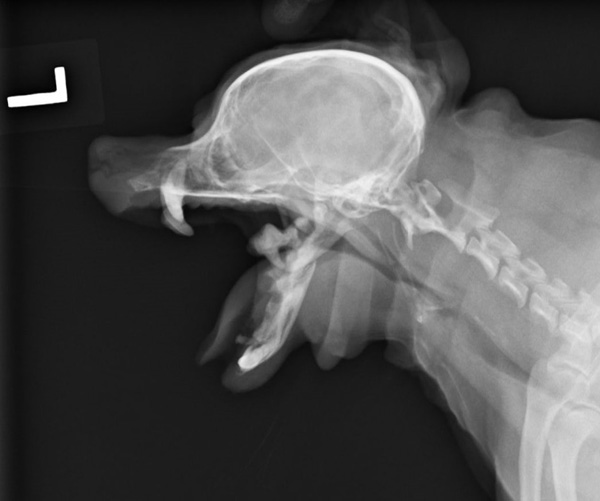

重度の歯周病で両側の下顎の病的骨折をしているワンちゃんが来院されました。悪い歯の抜歯と下顎のプレート固定(TITAN LOCK1.2mm使用)で対応しました。退院後しっかりご飯が食べられるようになりました。よかったね。